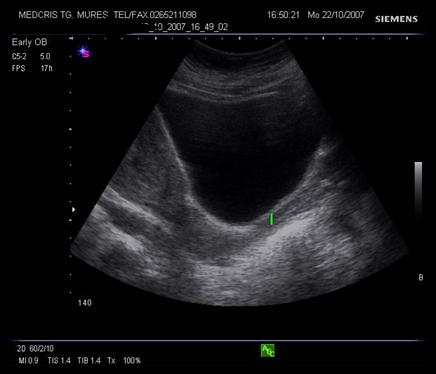

Fig. nr. 236.

Fig. nr.232. Ecografie abdominala , cu sectiunea sagitala a vaginului ( linia ), colului si istmului uterin, la o sarcina de 8 sapt.

Fig. nr.234. Col uterin evaluat prin ecografie transvaginala , la o sarcina de 26 saptamani cu iminenta de nastere prematura prin contractii uterine, se remarca lungimea sa normala, canalul cervical si orificiul cervical intern inchis

Fig. nr.235. Col incompetent la 24 saptamani, se remarca forma de V , la nivelui orificiului cervical intern, intre calipere